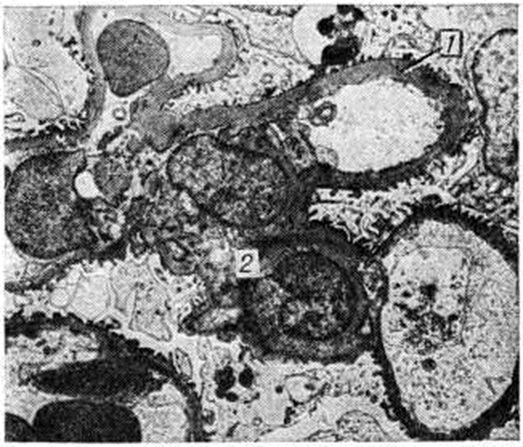

Диффузная форма выражается в однородном расширении и уплотнении мезангия с вовлечением в процесс базальных мембран капилляров, которые резко утолщены. Образующиеся в мезангии мембраноподобные структуры не сливаются в сплошные массы, и образования узелков не происходит. Базальные мембраны капиллярных петель клубочков утолщены, структура их исчезает (рисунок 2).

Рис. 2.

Микропрепарат почки при диффузной форме гломерулосклероза: значительная гиалинизация (1) интеркапиллярной (мезангиальной) области с утолщением базальных мембран (2) капилляров клубочка (окраска гематоксилин-эозином; ×350).